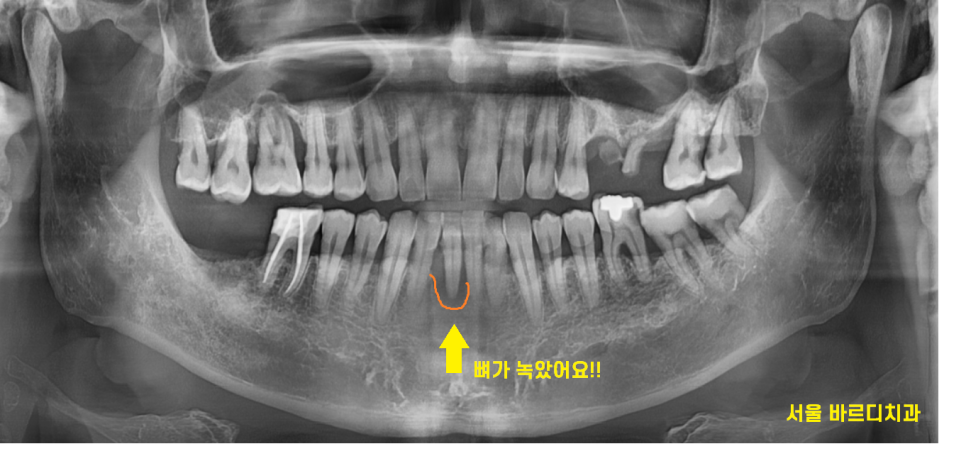

처음 내원하셨을 때

어금니, 앞니 여기저기 상실된 채로 내원하셨는데요.

아래 앞니가 제일 불편하다고 하셨는데요.

뼈가 많이 녹으면서

위로 솟았습니다.

손으로 뽑아도 뽑힐정도였으니ㅠㅠ

아래 앞니 임플란트 치료를 1순위로 하기로 결정했습니다.

문제는 치아 잇몸뼈가 너무 녹아서...

뼈가 없었습니다.